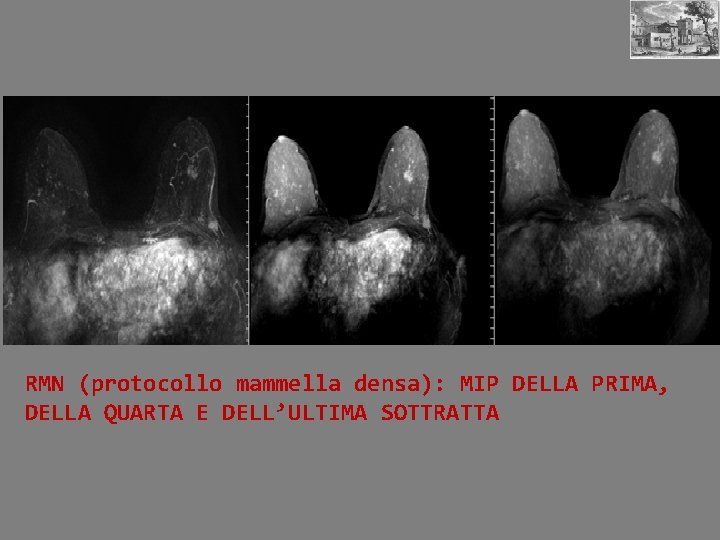

RMN (protocollo mammella densa): MIP DELLA PRIMA, DELLA QUARTA E DELL’ULTIMA SOTTRATTA